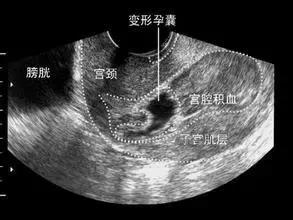

先兆流产:是妊娠28周前发生,先出现少量的阴道流血、继而出现阵发性下腹痛或腰痛,盆腔检查宫口未开,胎膜完整,无妊娠物排出,子宫大小与孕周相符。如果症状加重,可能发展为流产。